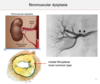

What are the clinical hallmarks of Tubulointerstitial Nephritis that distinguish it from Glomerular diseases?

- Absence of nephritic or nephrotic syndrome

- Defects in tubular function –> defect in concentrating urine = polyuria and nocturia

- Salt wasting

- Dimished ability to excrete acids (metabolic acidosis)